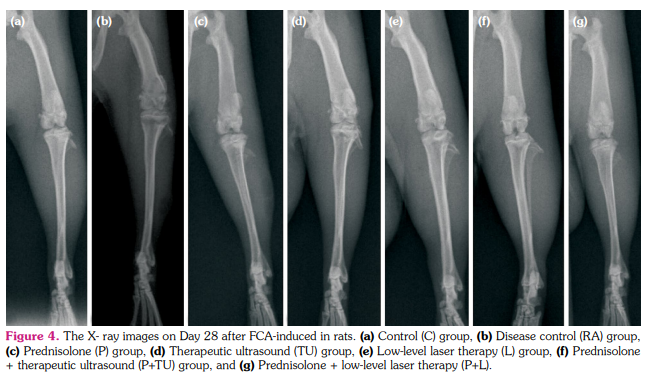

Radiological analysis

Before the begging of the study, the joints of rats were determined to be free of any radiological abnormality. The rats were anesthetized with sevoflurane and were positioned ventrodorsally on a table and X-ray image was obtained in the posterior-anterior view of the right knee joints with a stationary X-ray machine (Mex-100, Medical ECONET, Oberhausen, Germany) at 12 mA/s, 40 kV on Days 14 and 28. Two different blind observers performed radiological visual scoring, and visual scoring values were calculated based on the following conditions;[23] erosions: 0-3 (none, mild, moderate, severe); joint space narrowing: 0-3 (none, minimal, moderate, severe); joint space destruction: 0-3 (none, minimal, extensive, ankylosis).

Evaluation of radiological score

The radiological abnormality was not observed any time points in C groups (on Days 14 and 28 radiological score= 0, Table 1). The radiological score was not significantly different among groups on Day 14 (p>0.05, Figure 4). Compared to the RA groups (1.98±0.6), the mean radiological score was lower TU (1.55±0.5), P (1.45±0.5), L (1.45±0.1), P+TU (1.11±0.5), and P+L (1.05±0.3) group on Day 28 (Figure 4). The P+TU and P+L groups significantly decreased radiological scores at the end of the study (p<0.05, Figure 5). The P, TU, and L groups also decreased radiological scores, but were not statistically significant (p>0.05, Table 1).